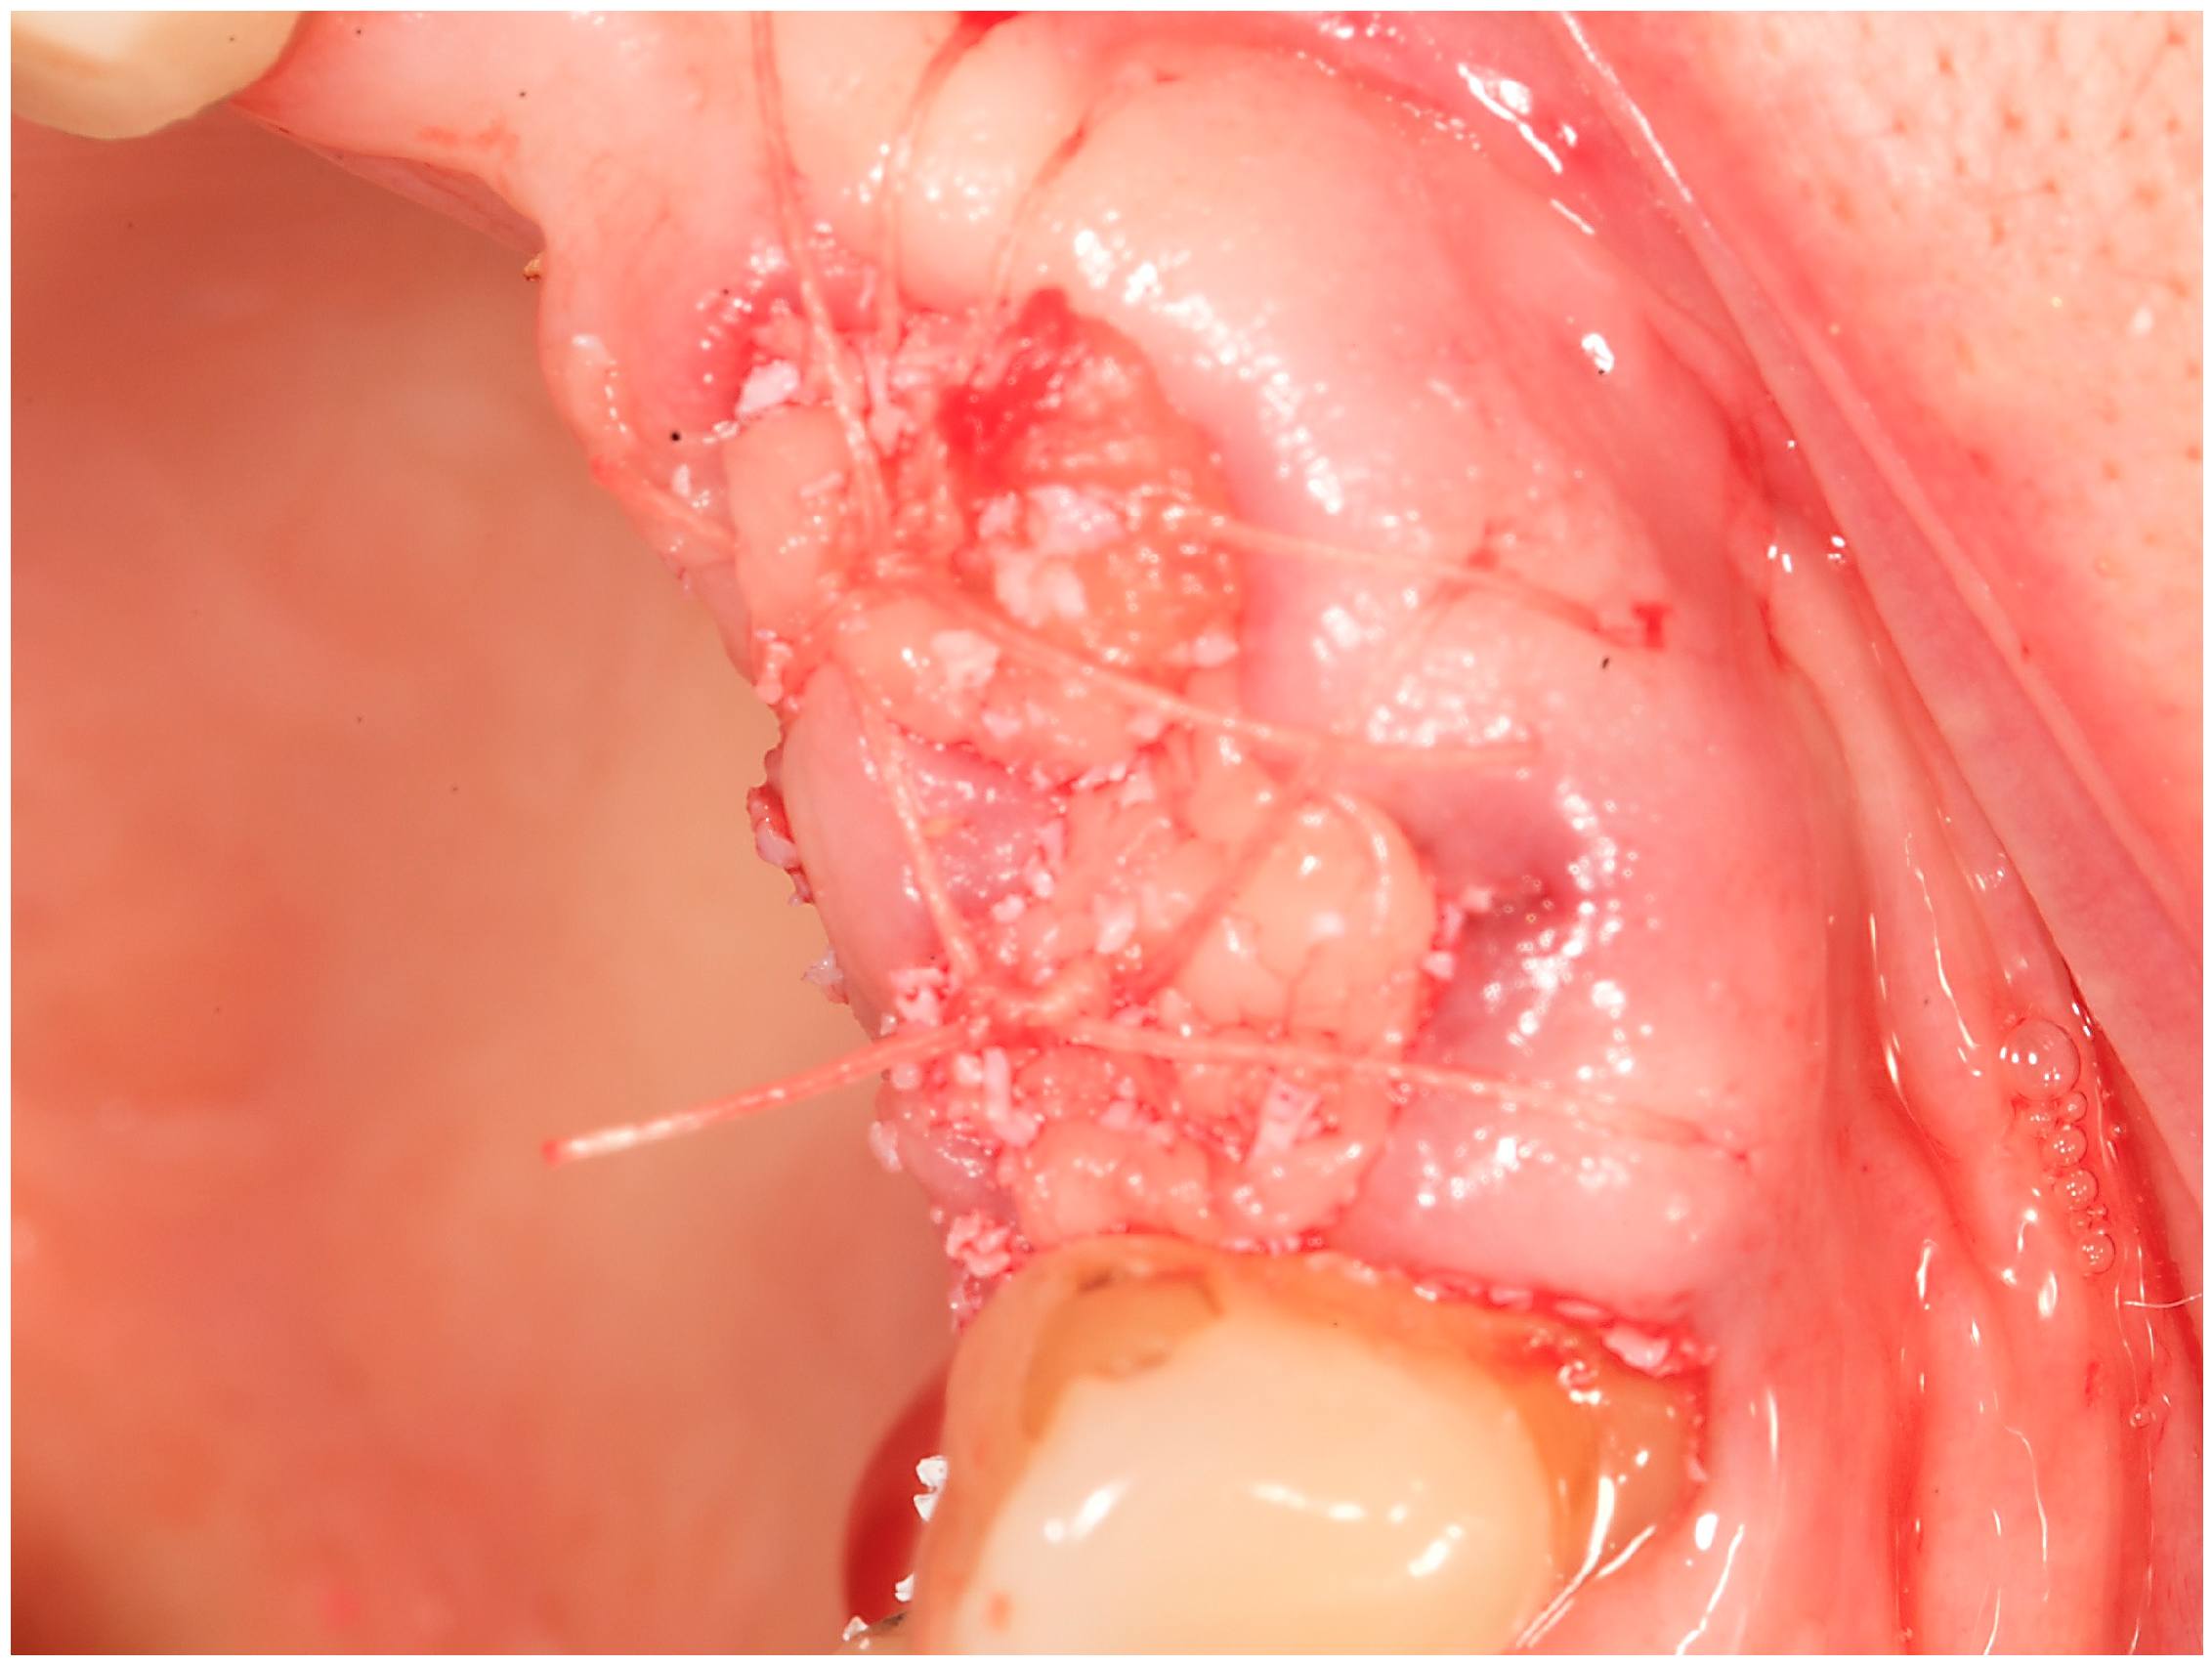

Case study 1